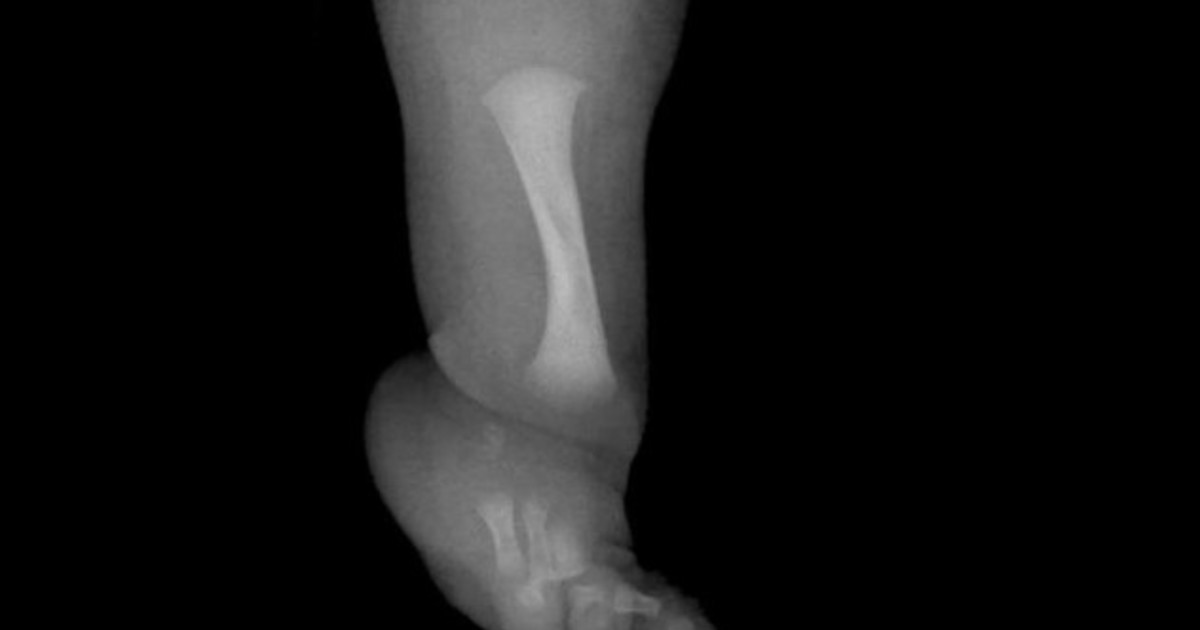

Un niño de nueve años se ha sometido en el Reino Unido a una cirugía pionera. Es para menores que tengan hemimelia fibular. Navegación de entradas Es latino, llegó a EE.UU. por trabajo y hoy es acusado de intentar ahogar a una mujer en Florida Quiniela de la Provincia: resultado del sorteo de la Primera de hoy, miércoles 18 de febrero